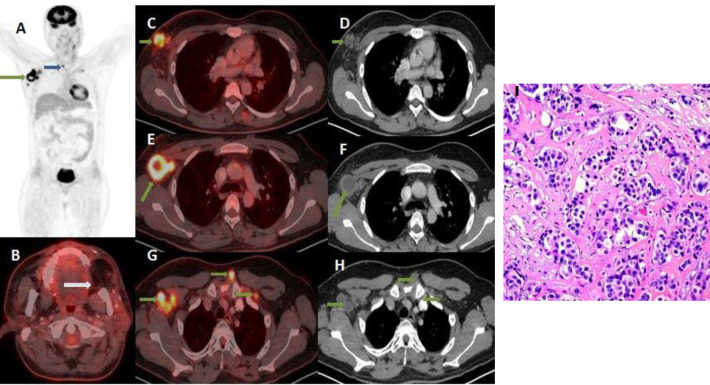

Results: On whole body 18F-FDG PET/CT, distant metastases were detected in 33 (11.7%) patients, all with locally advanced primary tumors corresponding to T category 3 and 4. Lung (6%) and bone (~6.7%) were the most common sites of distant metastasis. In nine patients metastases were detected below the diaphragm. Synchronous malignancies were discovered and histopathologically proven in 22 (7%) patients. Lung carcinoma was the most common synchronous tumor, detected in 9 patients. In seven patients synchronous tumour was detected outside the aerodigestive tract, of which four were below the diaphragm.

Conclusions: Of the distant metastasis diagnosed in 11.7% of HNC patients with TNM tumor category T3 and T4, 3% of metastasis lesions were detected below the diaphragm. Synchronous malignancy was diagnosed in 7% patients irrespective of primary HNC stage. These findings demonstrate the advantage of using whole body 18F-FDG PET/CT as an ideal and preferred modality for initial staging and screening of HNC patients since detection of distant metastasis or a synchronous malignancy changes the management approach in these patients.